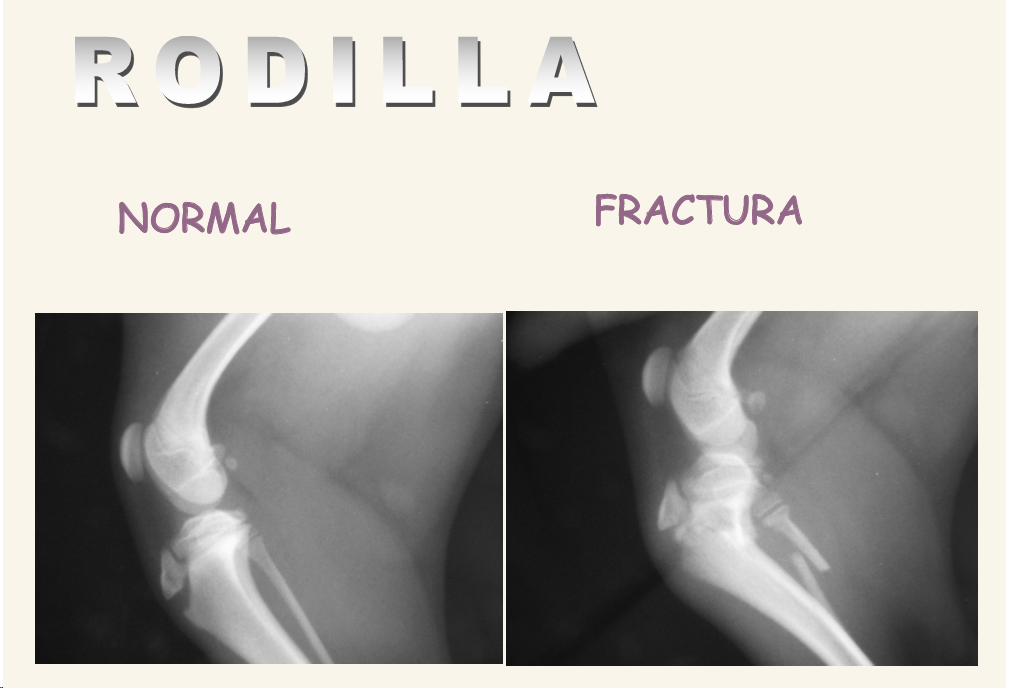

Rodilla

Proyecciones Media-Lateral y Caudo-Craneal o Craneal-Caudal con rodilla en posición neutra y cuña debajo del tarso para evitar rotación. Centrar en cóndilo femoral, en distal.

Hacer también proyecciones en estrés (ligamentos)

Cosas que podemos ver:

- Fracturas

- En cachorros muy comun las fracturas de rodilla en lineas de crecimiento en la meseta tibial

- El primer signo radiológico es el derrame, se pierde radiolucidez en tejido entre articulaciones (Disminución de la almohadilla grasa subrotuliana) , se ve gris en vez de negro bajo la rótula